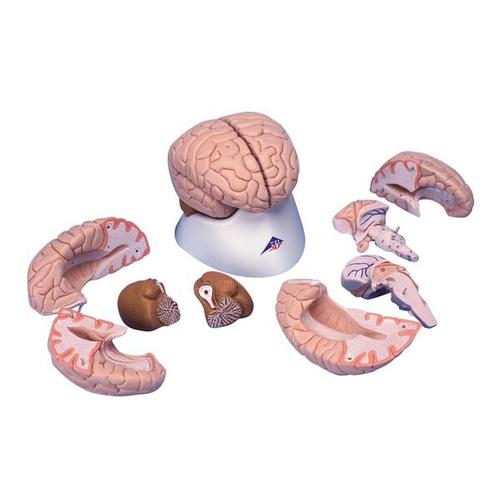

Bei diesem sehr detaillierten, median geschnittenen Modell sind beide Hälften zerlegbar in:

Stirn- mit Scheitellappen

Schläfen- mit Hinterhauptslappen

Hirnstamm

Kleinhirn

Auf abnehmbarem Sockel

Gewicht: 0,9 kg

Größe: 14 x 14 x 17.5 cm